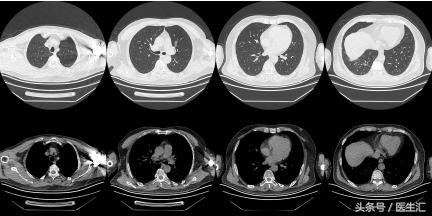

【 胸部 CT】2016.10.05

结果示:

本病例表现很普通,在临床上经常会碰到这种类型的,拿到这个病例首先可能会考虑是肺炎,但是真的是肺炎吗?为了明确诊断,再次详细问了患者的病史,下面来看看患者的病史特点,然后进行分析:

因为发现患者1 个月前有外伤手术史,那么是否可能有其他可能?所以我们给患者做了一个CTPA。

每一个层面都有肺动脉的充盈缺损。

治疗后复查胸部CT(2011.11.18)